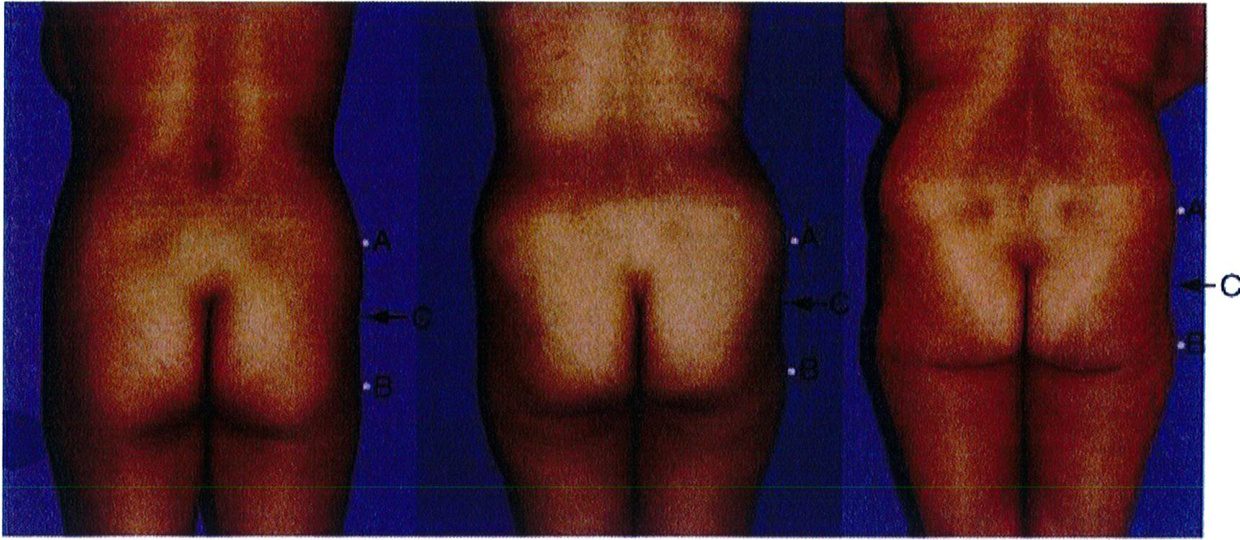

Điểm C có 2 chức năng: Đầu tiên là giúp phân biệt dạng mông tròn hay vuông. Mông tròn có lượng mỡ dư thừa ở điểm C này nhưng mông vuông thì có lượng mỡ bằng nhau hoặc lệch bên (Hình 5). Chức năng thứ hai và cũng là quan trọng nhất của điểm C là chúng giúp đánh giá mức độ lõm xuống ở điểm C trong mông vuông, mông hình chữ A hoặc hình chữ V. Mức độ lõm này được phân thành nhiều mức độ: 0, nhẹ, vừa, nặng (Hình 6).

Khung vuông là phổ biến nhất, gặp ở khoảng 40% số bệnh nhân. Vị trí A và B tương tự nhau, đặc trưng cho phần mông hình vuông để khi các điểm này nối với nhau sẽ được một hình vuông (Hình 7 và 8). Điểm C có thể có các mức độ lõm (thiếu mô mỡ) khác nhau. Đây là dạng khung dễ chỉnh hình nhất trong cả 4 kiểu khung vì bất kỳ sự thay đối nào ở 1 trong 3 điểm A,B,C đều có thể biến khung này thành dạng khung khác.

Ý nghĩa lâm sàng của điểm C là đối với những chỗ lõm nhẹ hoặc trung bình thường không cần ghép

Khung chữ A gặp ở khoảng 30% bệnh nhân. Khi nối các điểm A và B, tạo ra hình dạng gần như chữ A (Hình 11). Hình dạng này đặc biệt vì chúng tích nhiều mỡ ở hơn ở vùng đùi ngoài phía trên (điểm B) và ít chất béo hơn ở vùng hông bên (điểm A). Lý tưởng nhất là điểm A nhô ra nhiều hơn một chút. Lúc này, khi rút chất béo ở điểm B đi, mông bắt đầu có dạng vuông. Điểm C có thể bị lõm đi nhiều, song ở dạng này hầu hết các trường hợp chỉ lõm mức nhẹ hoặc trung bình.

Khung chữ A gặp ở khoảng 30% bệnh nhân. Khi nối các điểm A và B, tạo ra hình dạng gần như chữ A (Hình 11). Hình dạng này đặc biệt vì chúng tích nhiều mỡ ở hơn ở vùng đùi ngoài phía trên (điểm B) và ít chất béo hơn ở vùng hông bên (điểm A). Lý tưởng nhất là điểm A nhô ra nhiều hơn một chút. Lúc này, khi rút chất béo ở điểm B đi, mông bắt đầu có dạng vuông. Điểm C có thể bị lõm đi nhiều, song ở dạng này hầu hết các trường hợp chỉ lõm mức nhẹ hoặc trung bình. Dạng khung này thường được cải thiện khi hút mỡ ở điểm B hoặc vùng đùi bên (Hình 12). Điểm C có thể cần ghép mô mỡ, tùy thuộc vào mức độ lõm. Nên tránh hút mỡ quá nhiều ở điểm B để ngăn chặn điểm lõm ở khu vực này, ngẫu nhiên hình thành ranh giới giữa vùng mông và mặt ngoài đùi.

Hình. 11. Hình minh họa khung dạng chữ A với mức độ lõm nhẹ, trung bình và nhiều ở điểm C. Điểm A nên là điểm lồi ra nhiều nhất của vùng mông ở dạng này, nên sẽ thực hiện hút mỡ ở điểm B để cân đối lai.